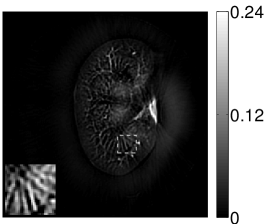

VI-E Results: kidney phantom

The images and EIRs reconstructed by use of the VP algorithm that was based on the 2D imaging model that neglected the SIR are shown in Figures 15 and 16. The latter figure contains results corresponding to different values for the regularization parameter . From Fig. 15, it can be observed that use of the conventional iterative method that utilized the measured EIR resulted in distortions and loss of details in the reconstructed images. Use of the VP algorithm improved the contrast and the details in the reconstructed images (Fig. 15(c) and 16(a)). Furthermore, the images reconstructed by use of the VP algorithm had a more uniform background.

In Figure 17, the results corresponding to use of the 3D imaging model that incorporated SIR effects are shown. The EIR estimated by the VP algorithm is also shown. In Figure 18, images and EIRs reconstructed by use of the VP algorithm with different regularization parameters values are shown.

Similar to the case described above where the transducer SIR was neglected, these results reveal that use of the VP algorithm can produce images with a cleaner background and enhanced spatial resolution than yielded by use of a conventional iterative algorithm that employed the measured EIR. For example, detailed information regarding the vessels near the organ’s periphery was better preserved by the VP algorithm than by the conventional iterative algorithm. These images corroborate our assertion that the VP algorithm can significantly reduce the artifacts and distortions in the reconstructed image. It is also worth pointing out that, unlike the numerical phantom studies, the artifacts and distortions in the images may be caused not only by the inaccurate EIR but also by other factors, such as neglecting acoustic heterogeneities and the variation of the EIRs among the elements of the transducer array. In such cases, the EIR estimated by the VP algorithm represents an effective system impulse response that minimizes the inconsistency between the measured data and the imaging model.